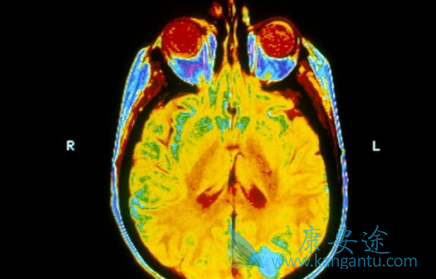

在之前使用过克唑替尼治疗的ROS1阳性NSCLC患者中,8例患者完全缓解,2例部分缓解,还有5例处于疾病稳定状态。颅内病灶的客观应答率为52.6%。这与之前没有使用克唑替尼治疗的队列相比,劳拉替尼对颅内病灶的客观缓解率数据都还是不错的(66.7% vs52.6%)。这也就是说,对于ROS1突变阳性的NSCLC患者,无论在使用劳拉替尼之前是否接受过克唑替尼治疗,劳拉替尼对颅内病灶的控制情况都可以表现出不错的能力。